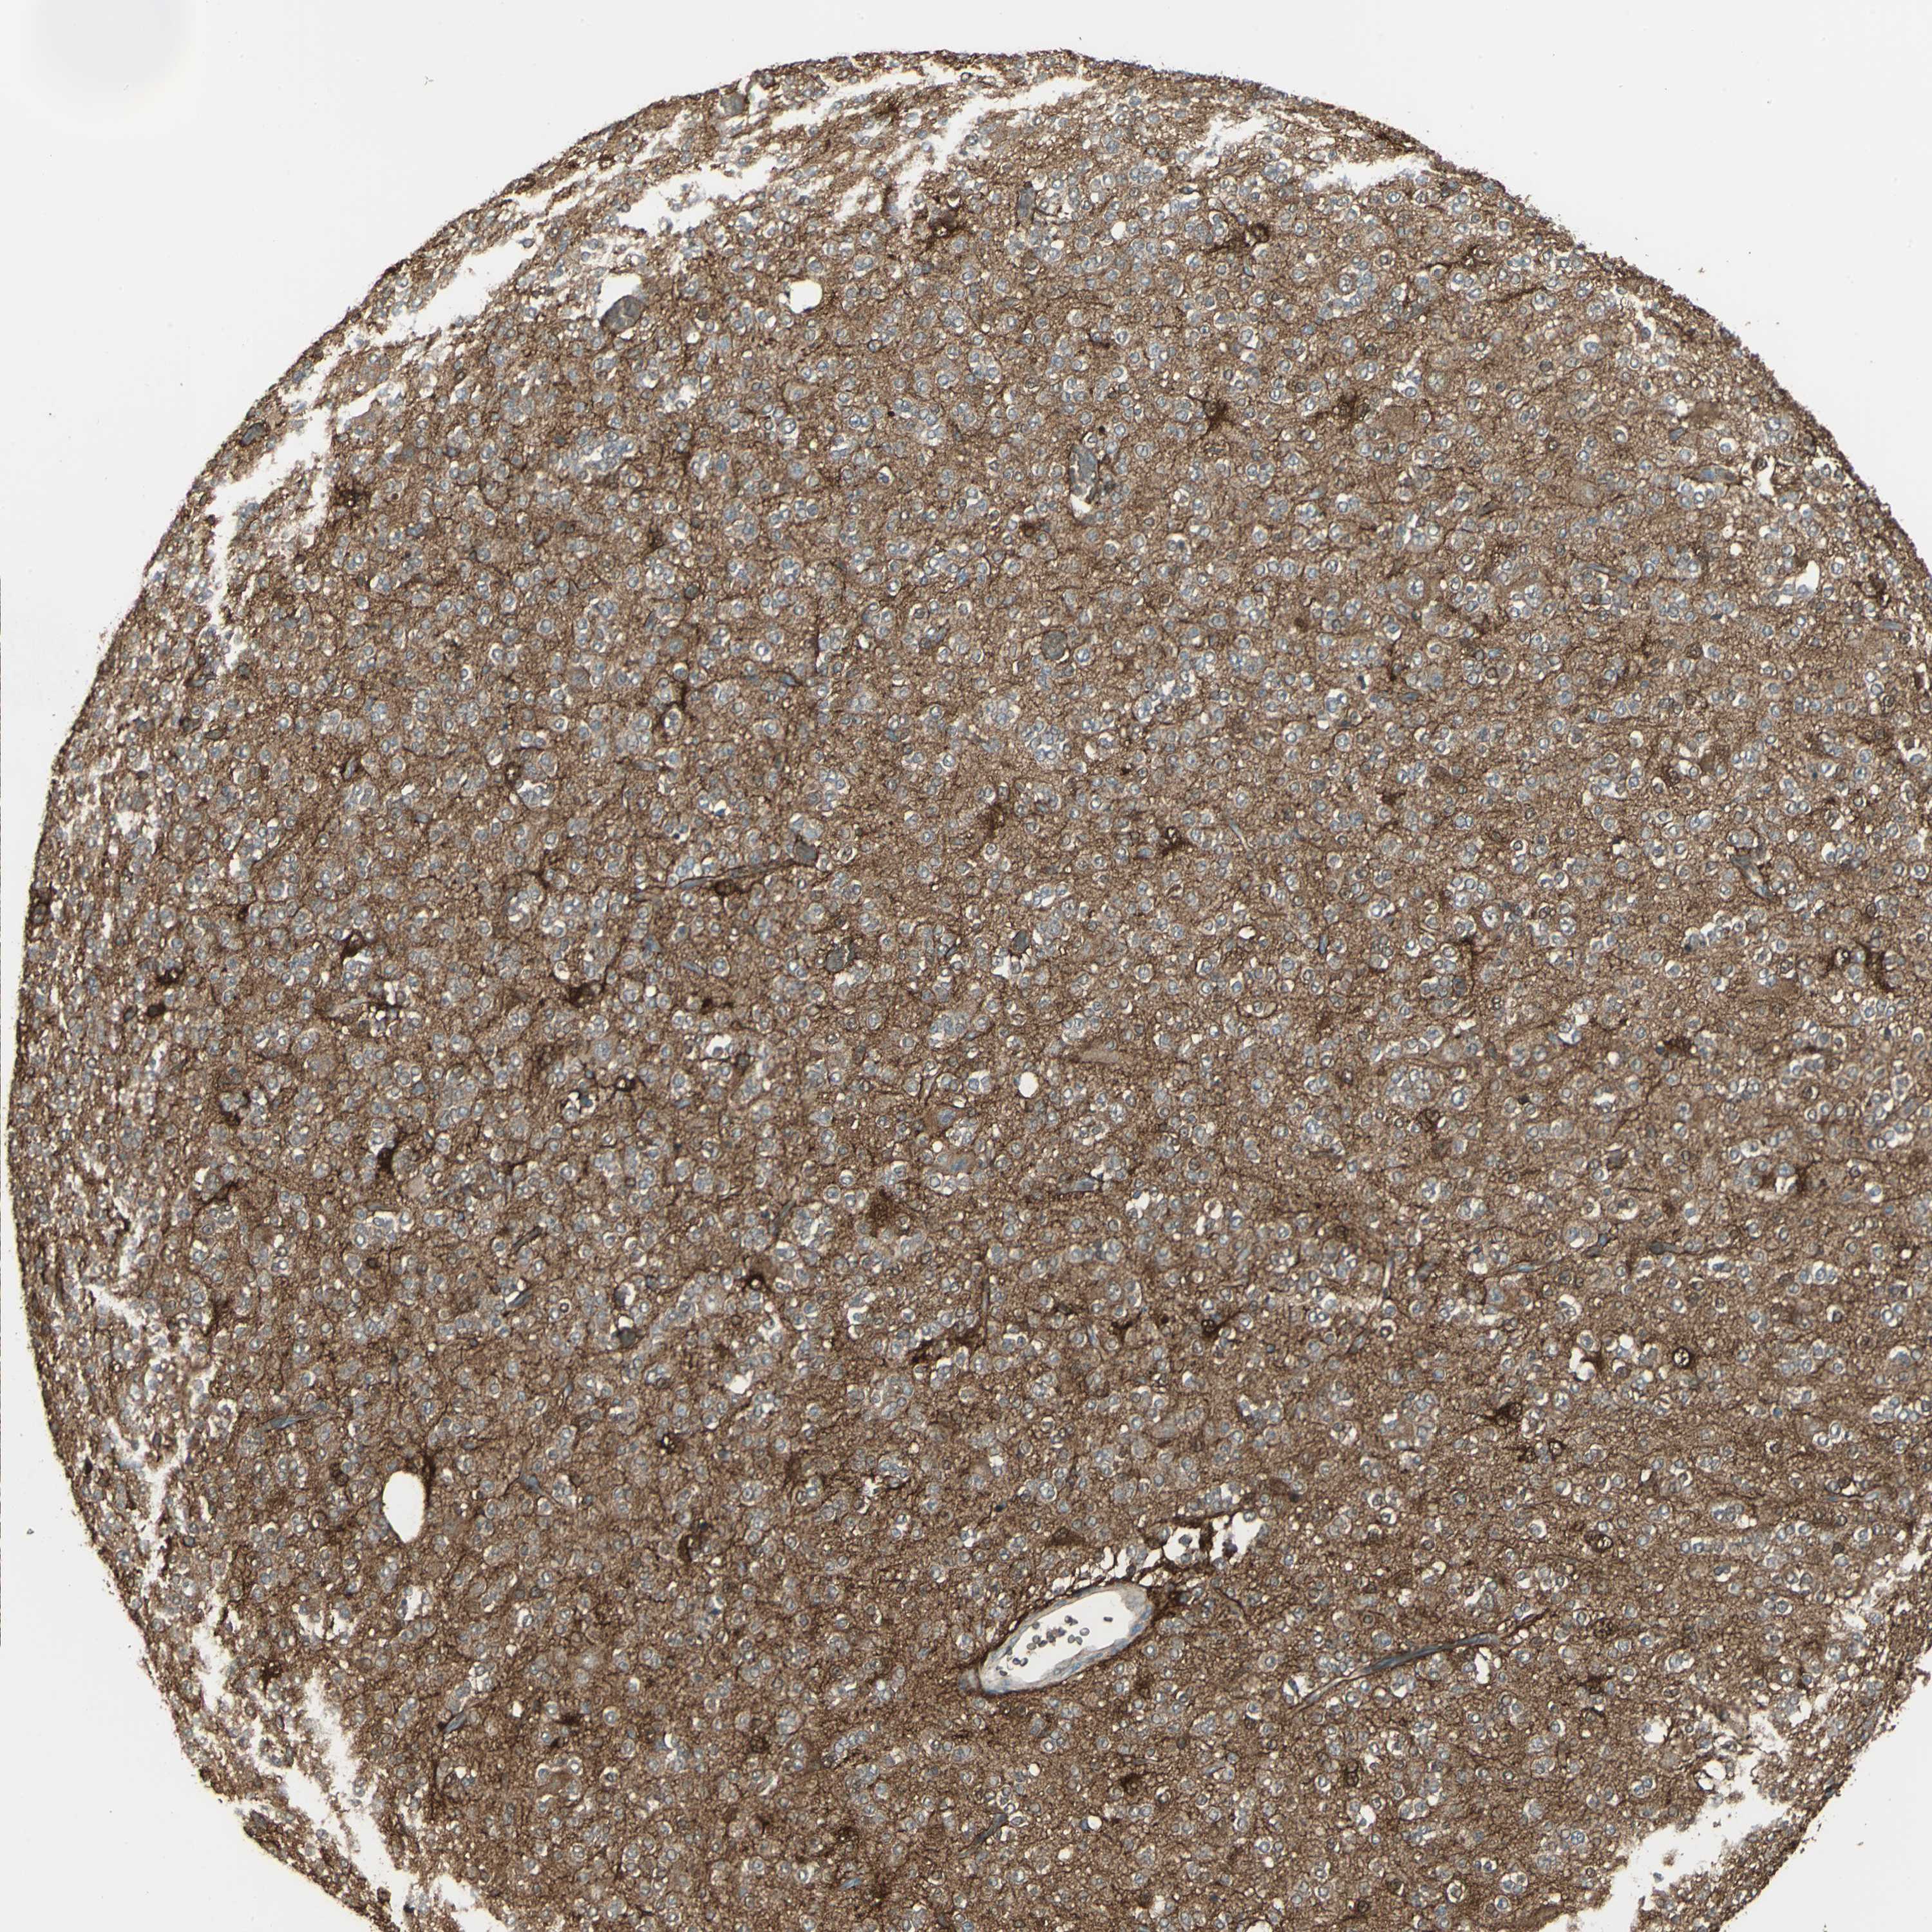

GLIOMA - Protein expressioni

A mouse-over function shows sample information and annotation data. Click on an image to view it in a full screen mode. Samples can be filtered based on level of antibody staining by selecting one or several of the following categories: high, medium, low and not detected. The assay and annotation is described here.

Note that samples used for immunohistochemistry by the Human Protein Atlas do not correspond to samples in the TCGA dataset.

Antibody stainingi

Antibody staining in the annotated cell types in the current human tissue is reported as not detected, low, medium, or high, based on conventional immunohistochemistry profiling in selected tissues. This score is based on the combination of the staining intensity and fraction of stained cells.

Each image is clickable and will lead to virtual microscopy that enables deeper exploration of all samples and also displays staining intensity scores, fraction scores and subcellular localization as well as patient and tissue information for each sample.

Antibody HPA006308

Antibody HPA071064

Glioma, malignant, Low grade

Glioma, malignant, High grade